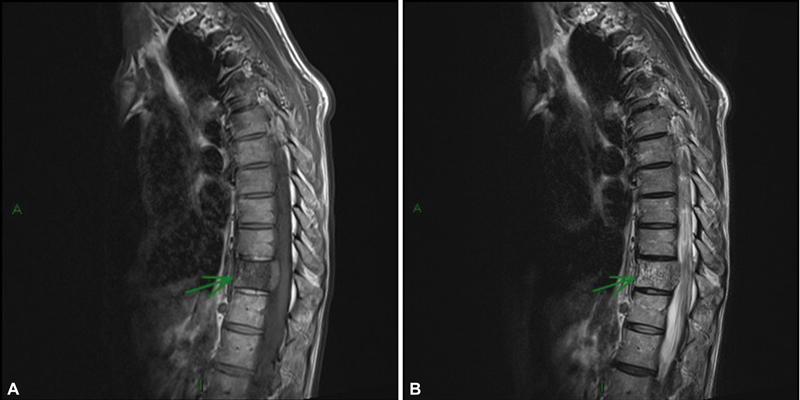

Collisions lesions are rare neoplasms where two histologically distinct tumors coexist in the same organ or anatomical site. Vertebral hemangiomas (VHs) are the most common lesions involving the vertebral bodies and imaging findings of typical and atypical hemangiomas, variant forms of hemangioma such as aggressive hemangiomas are well known, but collision lesions involving VHs are extremely rare. This article presents a case report of a 73-year-old male patient diagnosed with clear cell renal cancer in a rare presentation of a bone metastasis coinciding with the same anatomical position as a VH (collision lesion). This required a multidisciplinary approach involving various diagnostic techniques to determine the best therapeutic management.